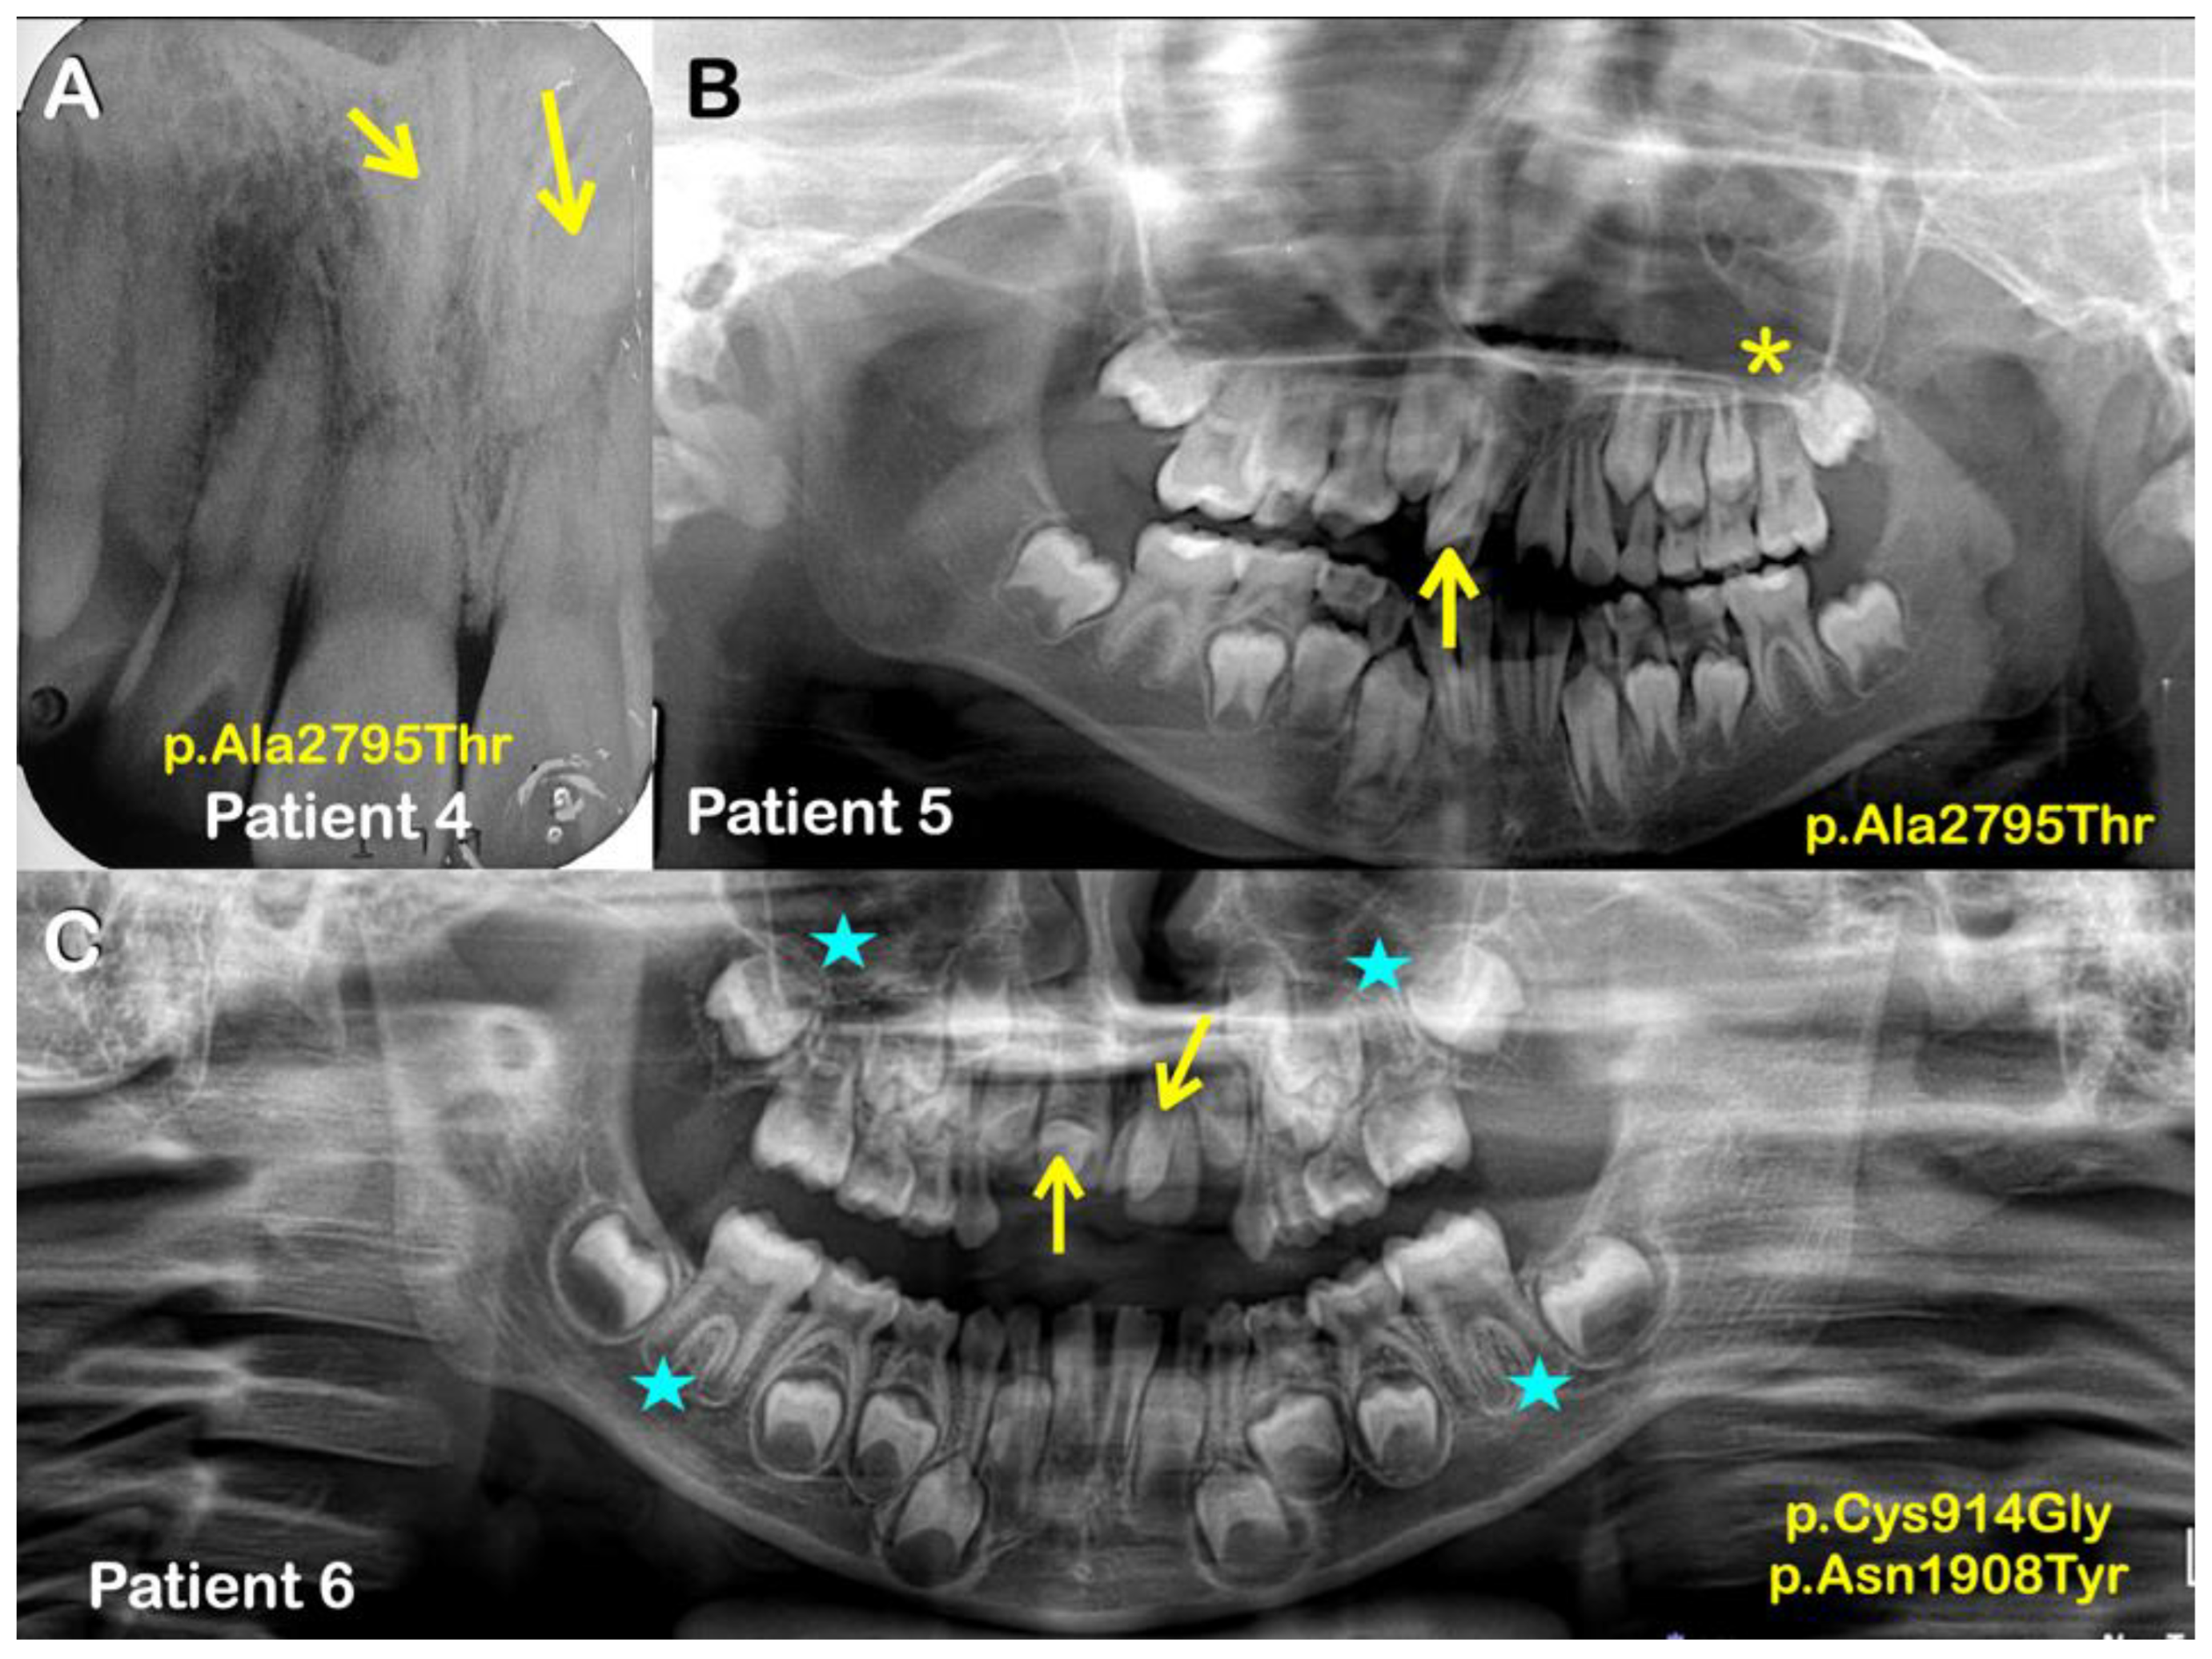

| Families | Patients | Phenotypes | APC Variants NM_000038.6; NP_000029.2 | Prediction/Ranking |

|---|---|---|---|---|

| 1 | 1 (Female) | Supernumerary erupted mandibular left premolar | c.3374T>C p.Val1125Ala chr5-112174665-T-C rs377278397 MAF: 0.0005993 | MutationTaster: Disease causing Prob = 0.944130296883564 Polyphen-2: Benign; score = 0.001 SIFT: Tolerated; score = 0.244 CADD-PHRED score = 21.7 DANN: Benign; score = 0.9507 |

| 2 | 2 (Male) | Mesiodens (Double with normal orientation) | ||

| 3 | 3 (Female) | Mesiodens (Single; erupted) | c.6127A>G p.Ile2043Val chr5-112177418-A-G rs876660233 MAF: 0.000007085 | MutationTaster: Disease causing Prob = 0.999923872840111 Polyphen-2: Probably damaging; score = 0.958 SIFT: Damaging; score = 0.011 CADD-PHRED score = 24.9 DANN score = 0.9983 |

| 4 | Normal mother | No variants | MutationTaster: Disease causing Prob = 0.999223891277048 Polyphen-2: Probably damaging; score = 0.936 SIFT: Tolerated; score = 0.068 CADD-PHRED score = 22.2 DANN score = 0.9909 | |

| 4 (Male) | Mesiodens (Double; unerupted & inverted) | c.8383G>A p.Ala2795Thr chr5-112179674-G-A rs369264968 MAF:0.00004400 | ||

| 5 (Male) | Mesiodens (Double; both were erupted) | |||

| Normal sister | No variants | |||

| 5 | 6 (Male) | Mesiodens (Double; unerupted) One is inverted, the other had normal orientation | Variant 1 c.2740T>G p.Cys914Gly chr5-112174031-T-G rs1554084426 Not reported in gnomAD Variant 2 c.5722A>T p.Asn1908Tyr chr5-112177013-A-T No rs number Not reported in gnomAD | Variant 1 MutationTaster: Disease causing Prob = 0.99929839701033 Polyphen-2: Benign score = 0.055 SIFT: Tolerated; score = 0.127 CADD-PHRED score = 21.5 DANN score = 0.8956 Variant 2 MutationTaster: Polymorphism Prob = 0.999999988244843 Polyphen-2: Benign score = 0.214 SIFT: Damaging; score = 0.046 CADD-PHRED score = 17.19 DANN score = 0.9609 |